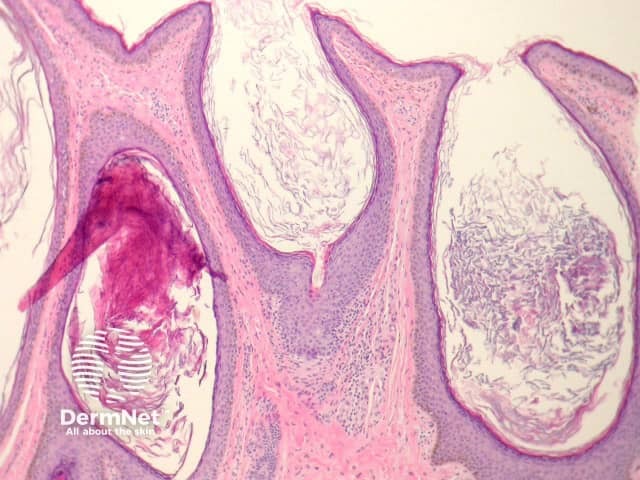

Comedones are follicular retention cysts which may open directly to the surface (open comedone or “blackhead”) or have a blocked surface (closed comedone or “whitehead”).

Sections of open comedones show massive follicular dilation (figure 1). The dilated follicles are filled with keratin (figure 2). These may be filled with cellular debris and/or inflammatory cells. Closed comedones do not show a patent follicular channel to the surface (figure 3).

Figure 2